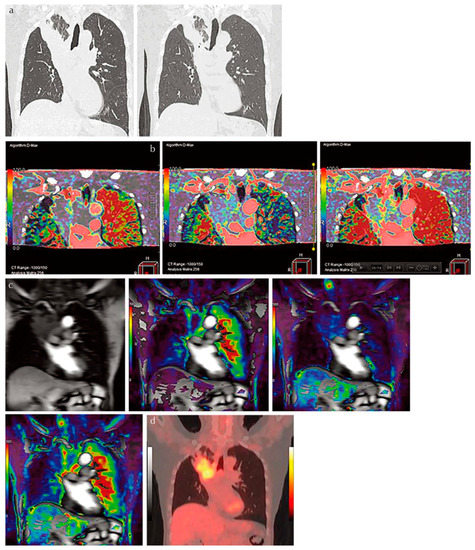

Few studies have been published on radiation dose reduction for the use of ADCT for the quantitative assessment of morphological evaluation of ILD. However, the utility of commercial or proprietary artificial intelligences (AIs) using machine-learning methods by Canon Medical Systems has been evaluated for the management of various lung diseases, such as ILD, or the evaluation of therapeutic treatments for coronavirus disease 2019 (COVID-19) pneumonia, which is caused by severe acute respiratory syndrome coronavirus 2 (SARS-CoV-2) [61,62,63] (Figure 2).

Figure 2.

A 65-year-old female patient with progressive scleroderma (top row, L to R: thin-section CT scans at baseline, acute exacerbation phase, and after-treatment phase; bottom row, L to R: CT texture analysis by means of machine-learning-based software at baseline and the same two phases as for the top row) (permission from reference [63]). On machine-learning software, normal lung, consolidation, emphysema, GGO, honeycombing and reticulation are expressed as blue, beige, purple, green, red and green. A comparison of CT scans obtained at baseline (i.e., “Stable” group) and at the acute exacerbation phase (i.e., “Worse” group) shows an increase in the GGO and the consolidation area and a decrease in the normal lung area. Δ% normal lung, Δ% GGO, and Δ% consolidation were −16.9%, 13.2%, and 2.5%, respectively, while Δ disease severity score was 6. A comparison of CT scans obtained at the acute exacerbation phase (i.e., “Worse” group) and the after-treatment phase (i.e., “Worse” group) shows an increase in the GGO, reticulation, and honeycomb area and a decrease in the normal lung area. Δ% normal lung, Δ% GGO, Δ% reticulation, and Δ% honeycomb were −19.5%, 14.9%, 4.2%, and 0.2%, while Δ disease severity score was 15. CT, computed tomography; GGO, ground-glass opacity.

These studies were the first to demonstrate the potential of AI in the evaluation of disease severity and therapeutic effect or of functional changes due to treatment with an accuracy similar to that attained by board-certified radiologists [61,62,63]. Although further investigations are warranted, the evaluation of ADCT by AI has opened new areas for the application of pulmonary functional ADCT in not only ILD but also other diseases.